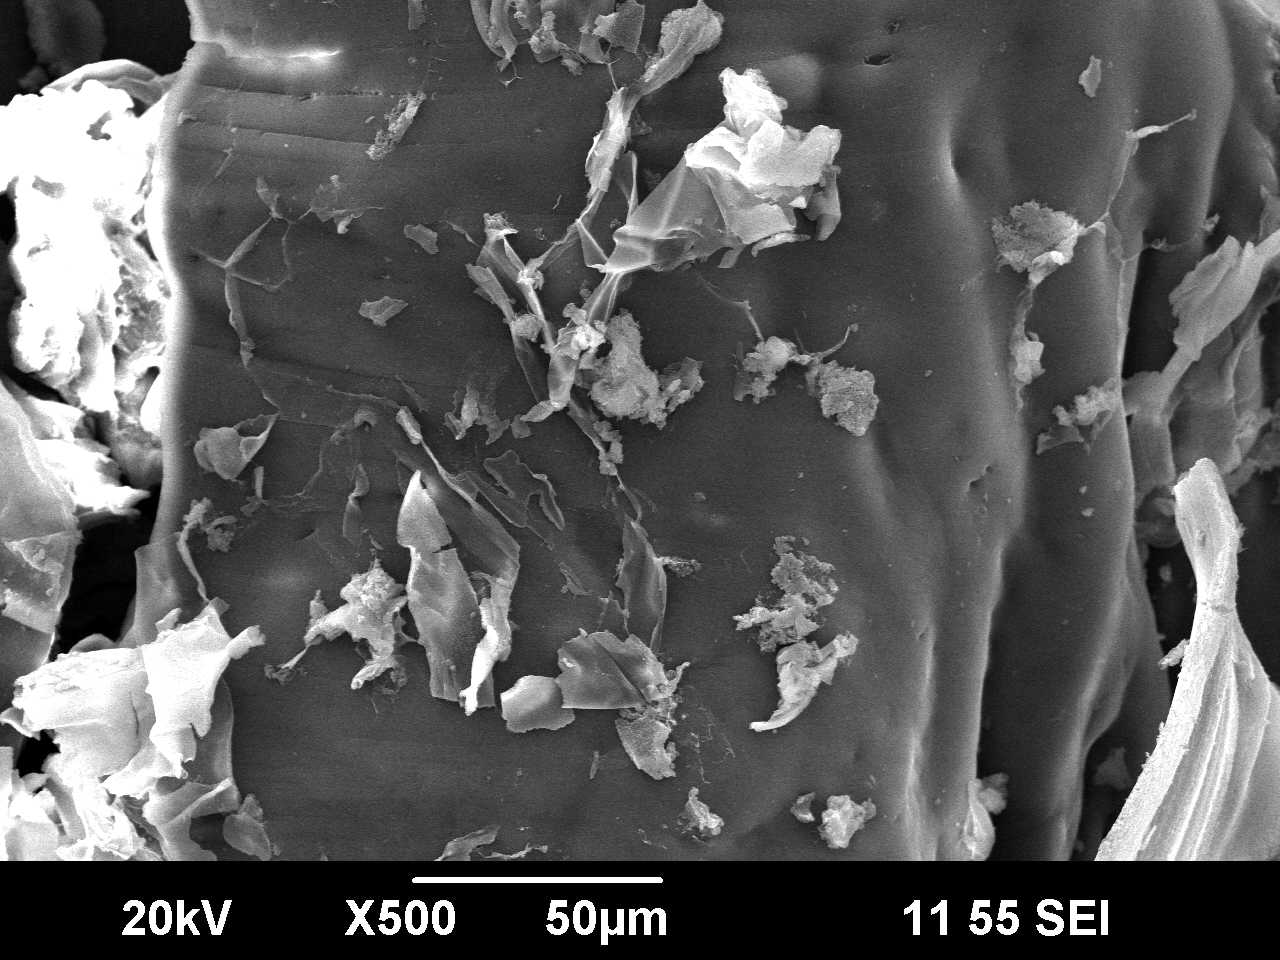

Scanning electron microscopy (SEM) was used to investigate particle surface morphology when comparing the surface of chitosan and eudragit s-100 (1:5) mixture with the surface of co-processed excipient (chitosan: eudragit s-100, 1:5) prepared using solvent evaporation method. It is apparent that its native structure has changed from a smooth, flat surface structure, with folded edges, to three-dimensional compacts for the eudragit s-100. This folding in the surface of the co-processed chitosan-eudragit s-100 creates a bigger surface area which can accommodate a larger quantity of eudragit s-100. As shown in Figure 4.

A

B

Fig. 4: Scanning electron micrograph of mixture of Chitosan + Eudragit s-100 (1:5) ratio (A)and of prepared co-processed excipient by solvent evaporation method (B)